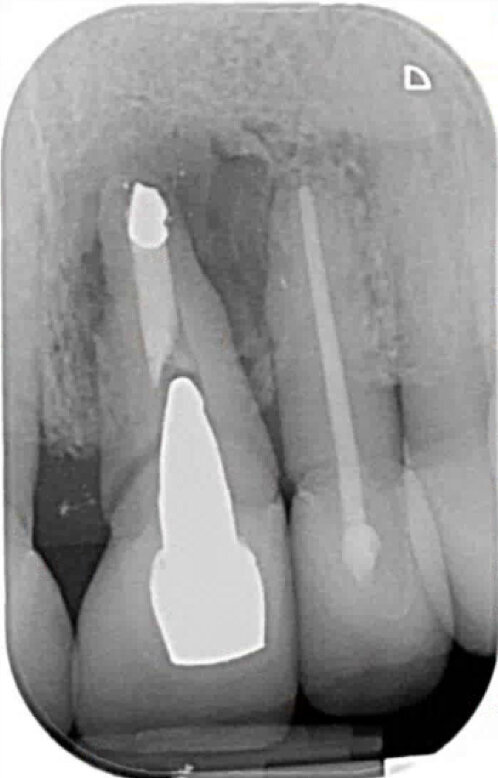

Fig. 8: Postoperative radiograph of implant placement.

We are routinely used to 2-D radiographic imaging techniques in dentistry, but with the availability and access to CBCT scanning devices now, we are able to assess bone quantity and quality of proposed implant surgical sites. With ever-reducing doses of 3-D imaging and improving accuracy, we are able to use CBCT scans, combined with clever software packages such as coDiagnostiX (Dental Wings), to plan safe and accurate implant placement and restoration. We are able to preoperatively plan precise implant placement with safe surgical margins away from important anatomical structures, such as the inferior alveolar nerve or maxillary sinus. From this, we are then able to design and either mill or print a surgical guide to use for precise implant placement.

Even with assisted surgery or guided surgery, there are sometimes certain restrictions that prevent us from achieving the most ideal implant placement, such as this case shown where posterior access in the second molar region was reduced, so achieving the perfect parallel was extremely difficult.